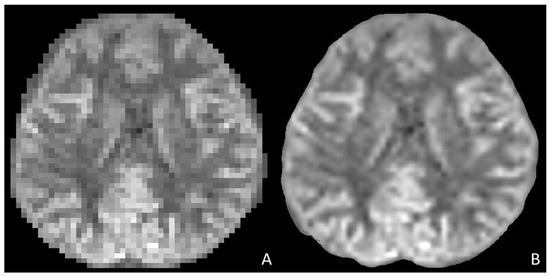

- Zhang, S.; Zhong, M.; Shenliu, H.; Wang, N.; Hu, S.; Lu, X.; Lin, L.; Zhang, H.; Zhao, Y.; Yang, C.; et al. Deep Learning-Based Super-Resolution Reconstruction on Undersampled Brain Diffusion-Weighted MRI for Infarction Stroke: A Comparison to Conventional Iterative Reconstruction. AJNR Am. J. Neuroradiol. 2025, 46, 41–48. [Google Scholar] [CrossRef]

- Matsuo, K.; Nakaura, T.; Morita, K.; Uetani, H.; Nagayama, Y.; Kidoh, M.; Hokamura, M.; Yamashita, Y.; Shinoda, K.; Ueda, M.; et al. Feasibility Study of Super-Resolution Deep Learning-Based Reconstruction Using K-Space Data in Brain Diffusion-Weighted Images. Neuroradiology 2023, 65, 1619–1629. [Google Scholar] [CrossRef]